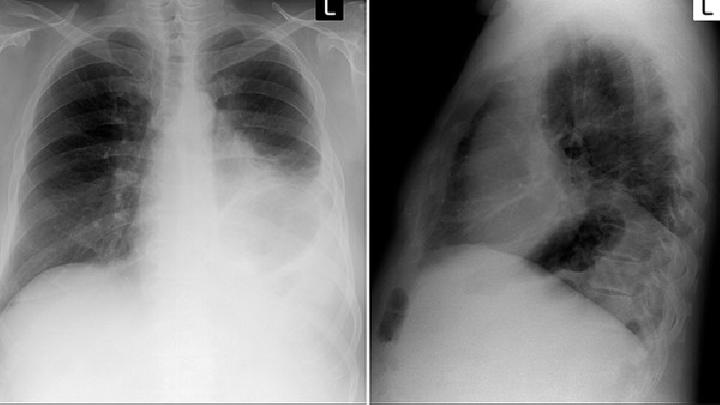

肺转移瘤

肺转移瘤晚期症状有哪些